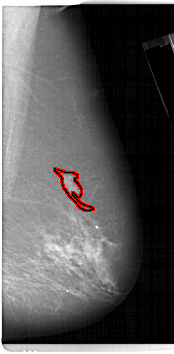

A_1144_1.LEFT_MLO

LEFT_MLO LINES 6721 PIXELS_PER_LINE 3886 BITS_PER_PIXEL 12 RESOLUTION 43.5 NON_OVERLAY

FILE: A_1144_1.RIGHT_CC.OVERLAY

TOTAL_ABNORMALITIES 1

ABNORMALITY 1

LESION_TYPE MASS SHAPE IRREGULAR MARGINS ILL_DEFINED

ASSESSMENT 4

SUBTLETY 4

PATHOLOGY MALIGNANT

TOTAL_OUTLINES 1

BOUNDARY